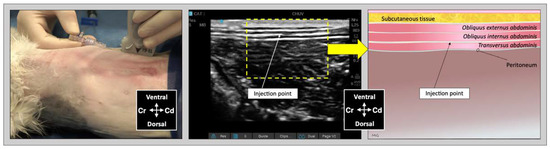

For the lateral TAP injection, the transducer was positioned parallel to the long axis of the cat (longitudinal plane), at 3–4 cm lateral to the abdominal midline and about 1 cm lateral to the mammary line, immediately caudal to the last rib (Figure 2). The transducer was slide laterally until the belly of the m. obliquus internus abdominis could be identified between the mm. obliquus externus and transversus abdominis. The needle was introduced in-plane in a ventrocranial-to-dorsocaudal orientation and continually visualized until its tip was advanced into the TAP between the m. obliquus internus abdominis and the m. transversus abdominis (Figure 2). Then, the assigned injectate volume was administered (0.5 mL/kg in TAP-L versus 0.25 mL/kg in TAP-SL).

Figure 2. Ultrasound transducer position, needle puncture site, sonographic image, and schematic representation of the lateral TAP injection in a cat cadaver; Cd, caudal; Cr, cranial, L, lateral; Lt, left; M, medial; Rt, right. Adapted from: Garbin, M.; Benito, J.; Ruel, H.L.M.; Watanabe, R.; Monteiro, B.P.; Cagnardi, P.; Steagall, P.V. Pharmacokinetics of bupivacaine following administration by an ultrasound-guided transversus abdominis plane block in cats undergoing ovariohysterectomy. Pharmaceutics 2022, 14, 1548. https://doi.org/10.3390/pharmaceutics14081548 (accessed on 1 August 2022).